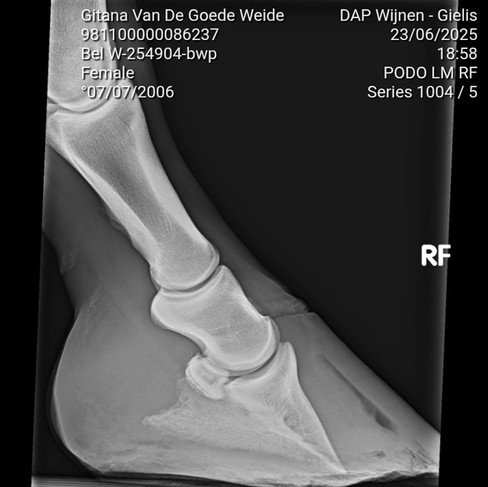

I have used Glushu on many complex cases and knew this would be a good solution. Here you can see a GluShu application with 12 degree wedge for the deep digital flexor tendon to be relieved. In addition I also employed a wedge during the shredding to get the hoof bone back into a good angle. To complete the job I filled the shoe with Shupack CS to provide counter-pressure.

The X-rays show before and after.